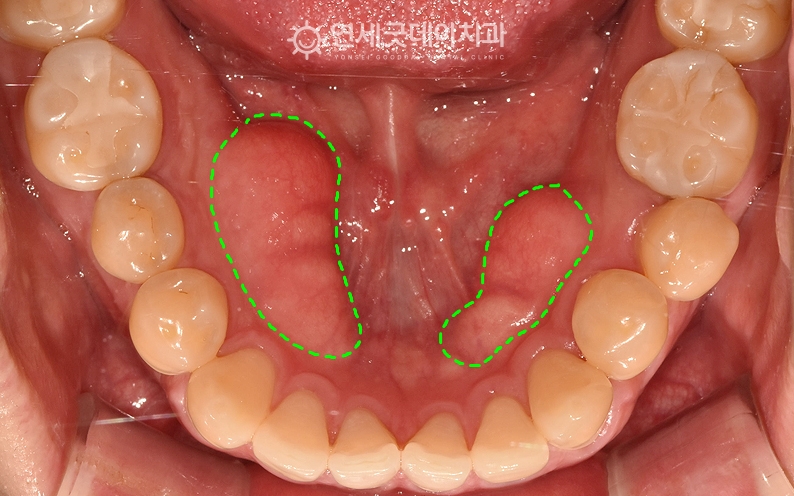

하악 골융기(토러스, torus) 제거, 치조골성형술 치료전후